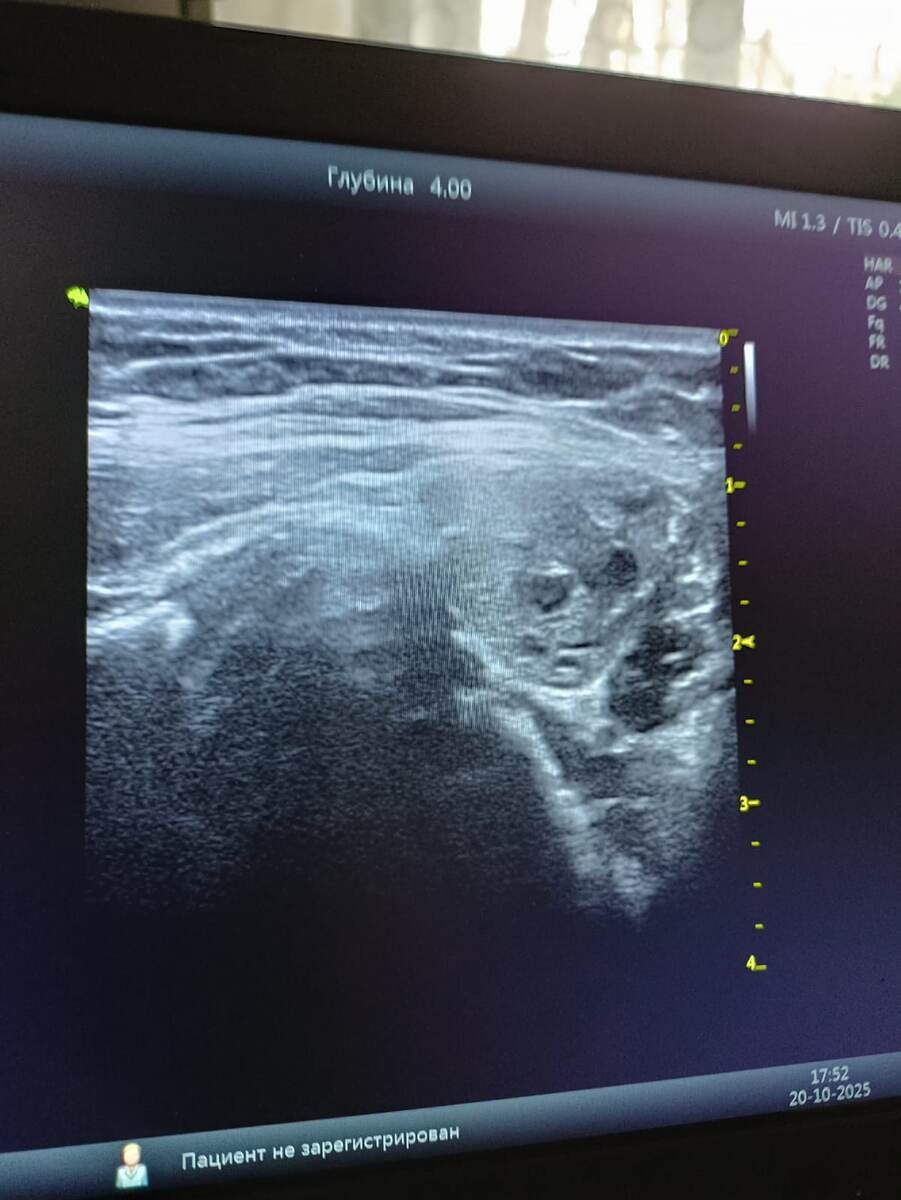

1. УЗИ щитовидной железы: что осталось после операции:

Краткий итог врача: «УЗ-картина соответствует послеоперационному состоянию. Признаков рецидива заболевания нет».

В 18 лет мне удалили щитовидку из-за узлового зоба. Прошло 15 лет. УЗИ подтвердило: правой доли

нет вообще, она полностью удалена. Левая доля сохранилась частично — её объем около 6.4 мл (это немного).

Самое главное, что искали и не нашли:

• Нет новых узлов или опухолей (очаговых образований).

• Нет увеличенных лимфоузлов на шее — это важный признак, что болезнь не вернулась.

• Нет активного воспаления (сосудистый рисунок не усилен).

Что есть и почему не стоит пугаться:

В заключении написано про «

неоднородную структуру», «неровные контуры» и «утолщённую капсулу». Это звучит тревожно, но врачи поясняют: это типичные послеоперационные рубцовые изменения. После любого хирургического вмешательства ткань заживает не идеально гладко, а именно так — с рубцами. Это не болезнь, а след.

Мой вывод и что мне с этим делать:

С точки зрения онкологии и хирургии —

всё спокойно. Рецидива нет. Но с точки зрения эндокринологии — своей функции у этой железы почти нет. Оставшегося кусочка категорически недостаточно, чтобы поддерживать гормональный баланс в организме. Это прямое подтверждение, почему мне жизненно необходимо принимать заместительную терапию (L-тироксин). Без неё гипотиреоз (дефицит гормонов) и все его последствия неизбежны.